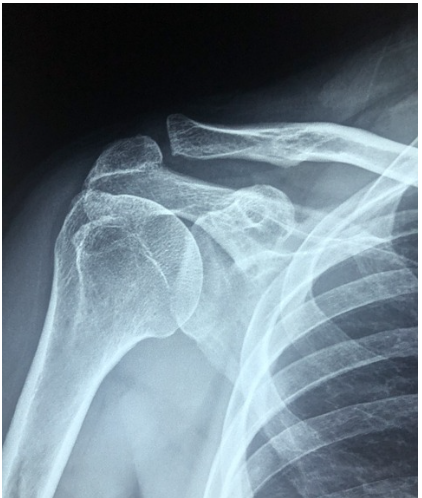

X-선 검사: 뼈의 상태를 확인하기 위해 X-선을 촬영하여 관절의 구조적 이상을 평가합니다.